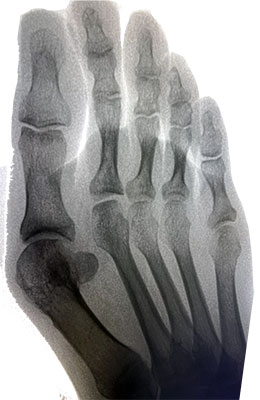

Before

After

Osteotomy Bunionectomy after

Osteotomy Bunionectomy

In this procedure (also known as an “Austin Bunionectomy), a cut in the bone was made, and the bone was shifted to realign the joint. A screw was placed to hold this new alignment in place. Notice the improved alignment of the great toe joint.